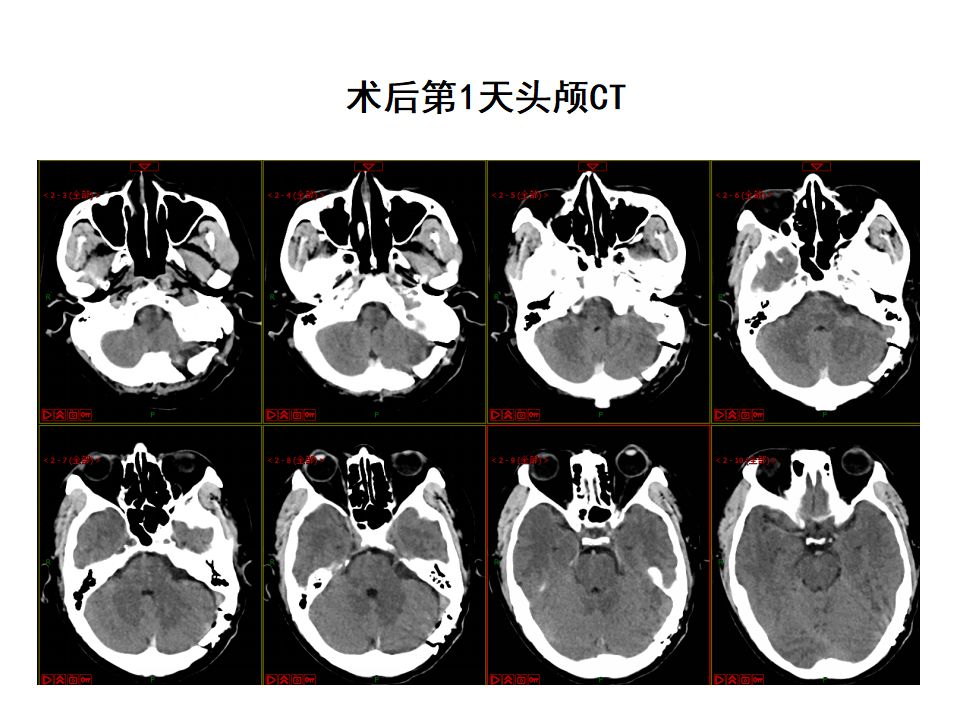

【病例分享】巨大囊性听神经瘤——唐都神经外科赵天智

图片尺寸1080x1246